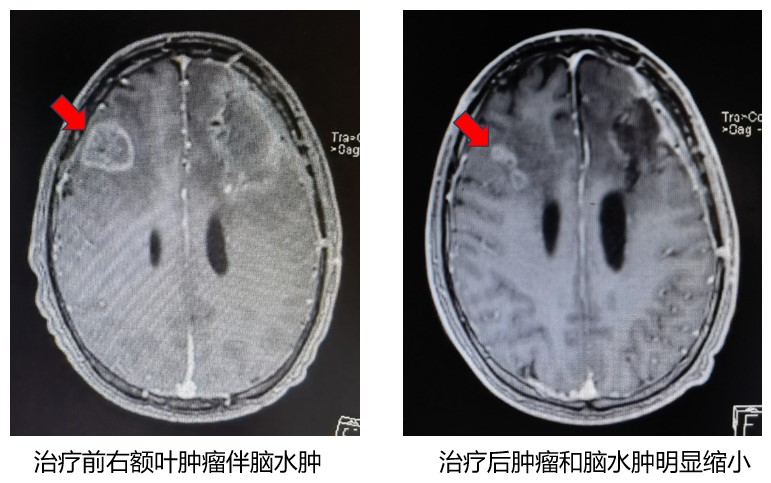

五、临床实际病例

病例1、老年男性,肺癌脑转移瘤,一侧肢体偏瘫,不能行走,不能自主活动。射波刀头部精准放疗3次,肿瘤和脑水肿完全消失,患者恢复自主活动,生活自理。

病例 2、中年男性,脑胶质母细胞瘤,四肢瘫痪卧床,不能自主活动。射波刀头部精准放疗3次,肿瘤缩明显缩小,脑水肿明显减轻,患者恢复自主活动。